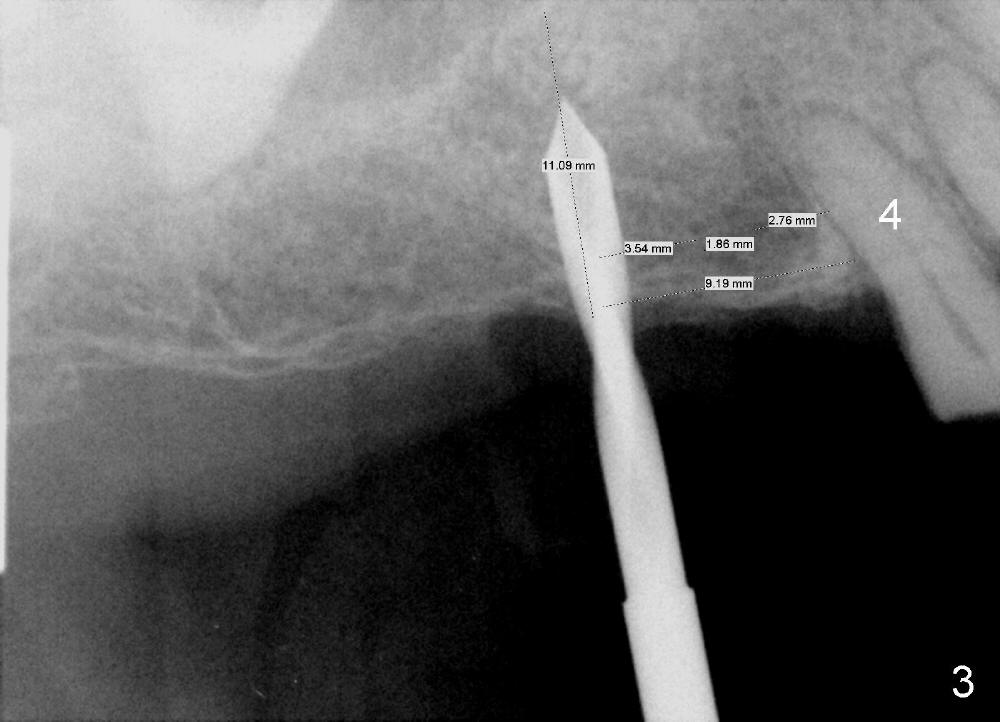

The pilot drill is easily penetrating the cancellous bone, suggesting low bone density. The remaining osteotomy is finished by bone expanders (Fig.4: 4.3 mm) and taps until 6x14 mm at gingival level. There is no sinus perforation when the 6x14 mm tap is removed from the osteotomy (Fig.5). Sinus lift is observed (Fig.6 arrowheads) when a 6x14 mm implant is placed with insertion toruqe > 60 Ncm. The distance to the adjacent tooth remains consistent to that of design.